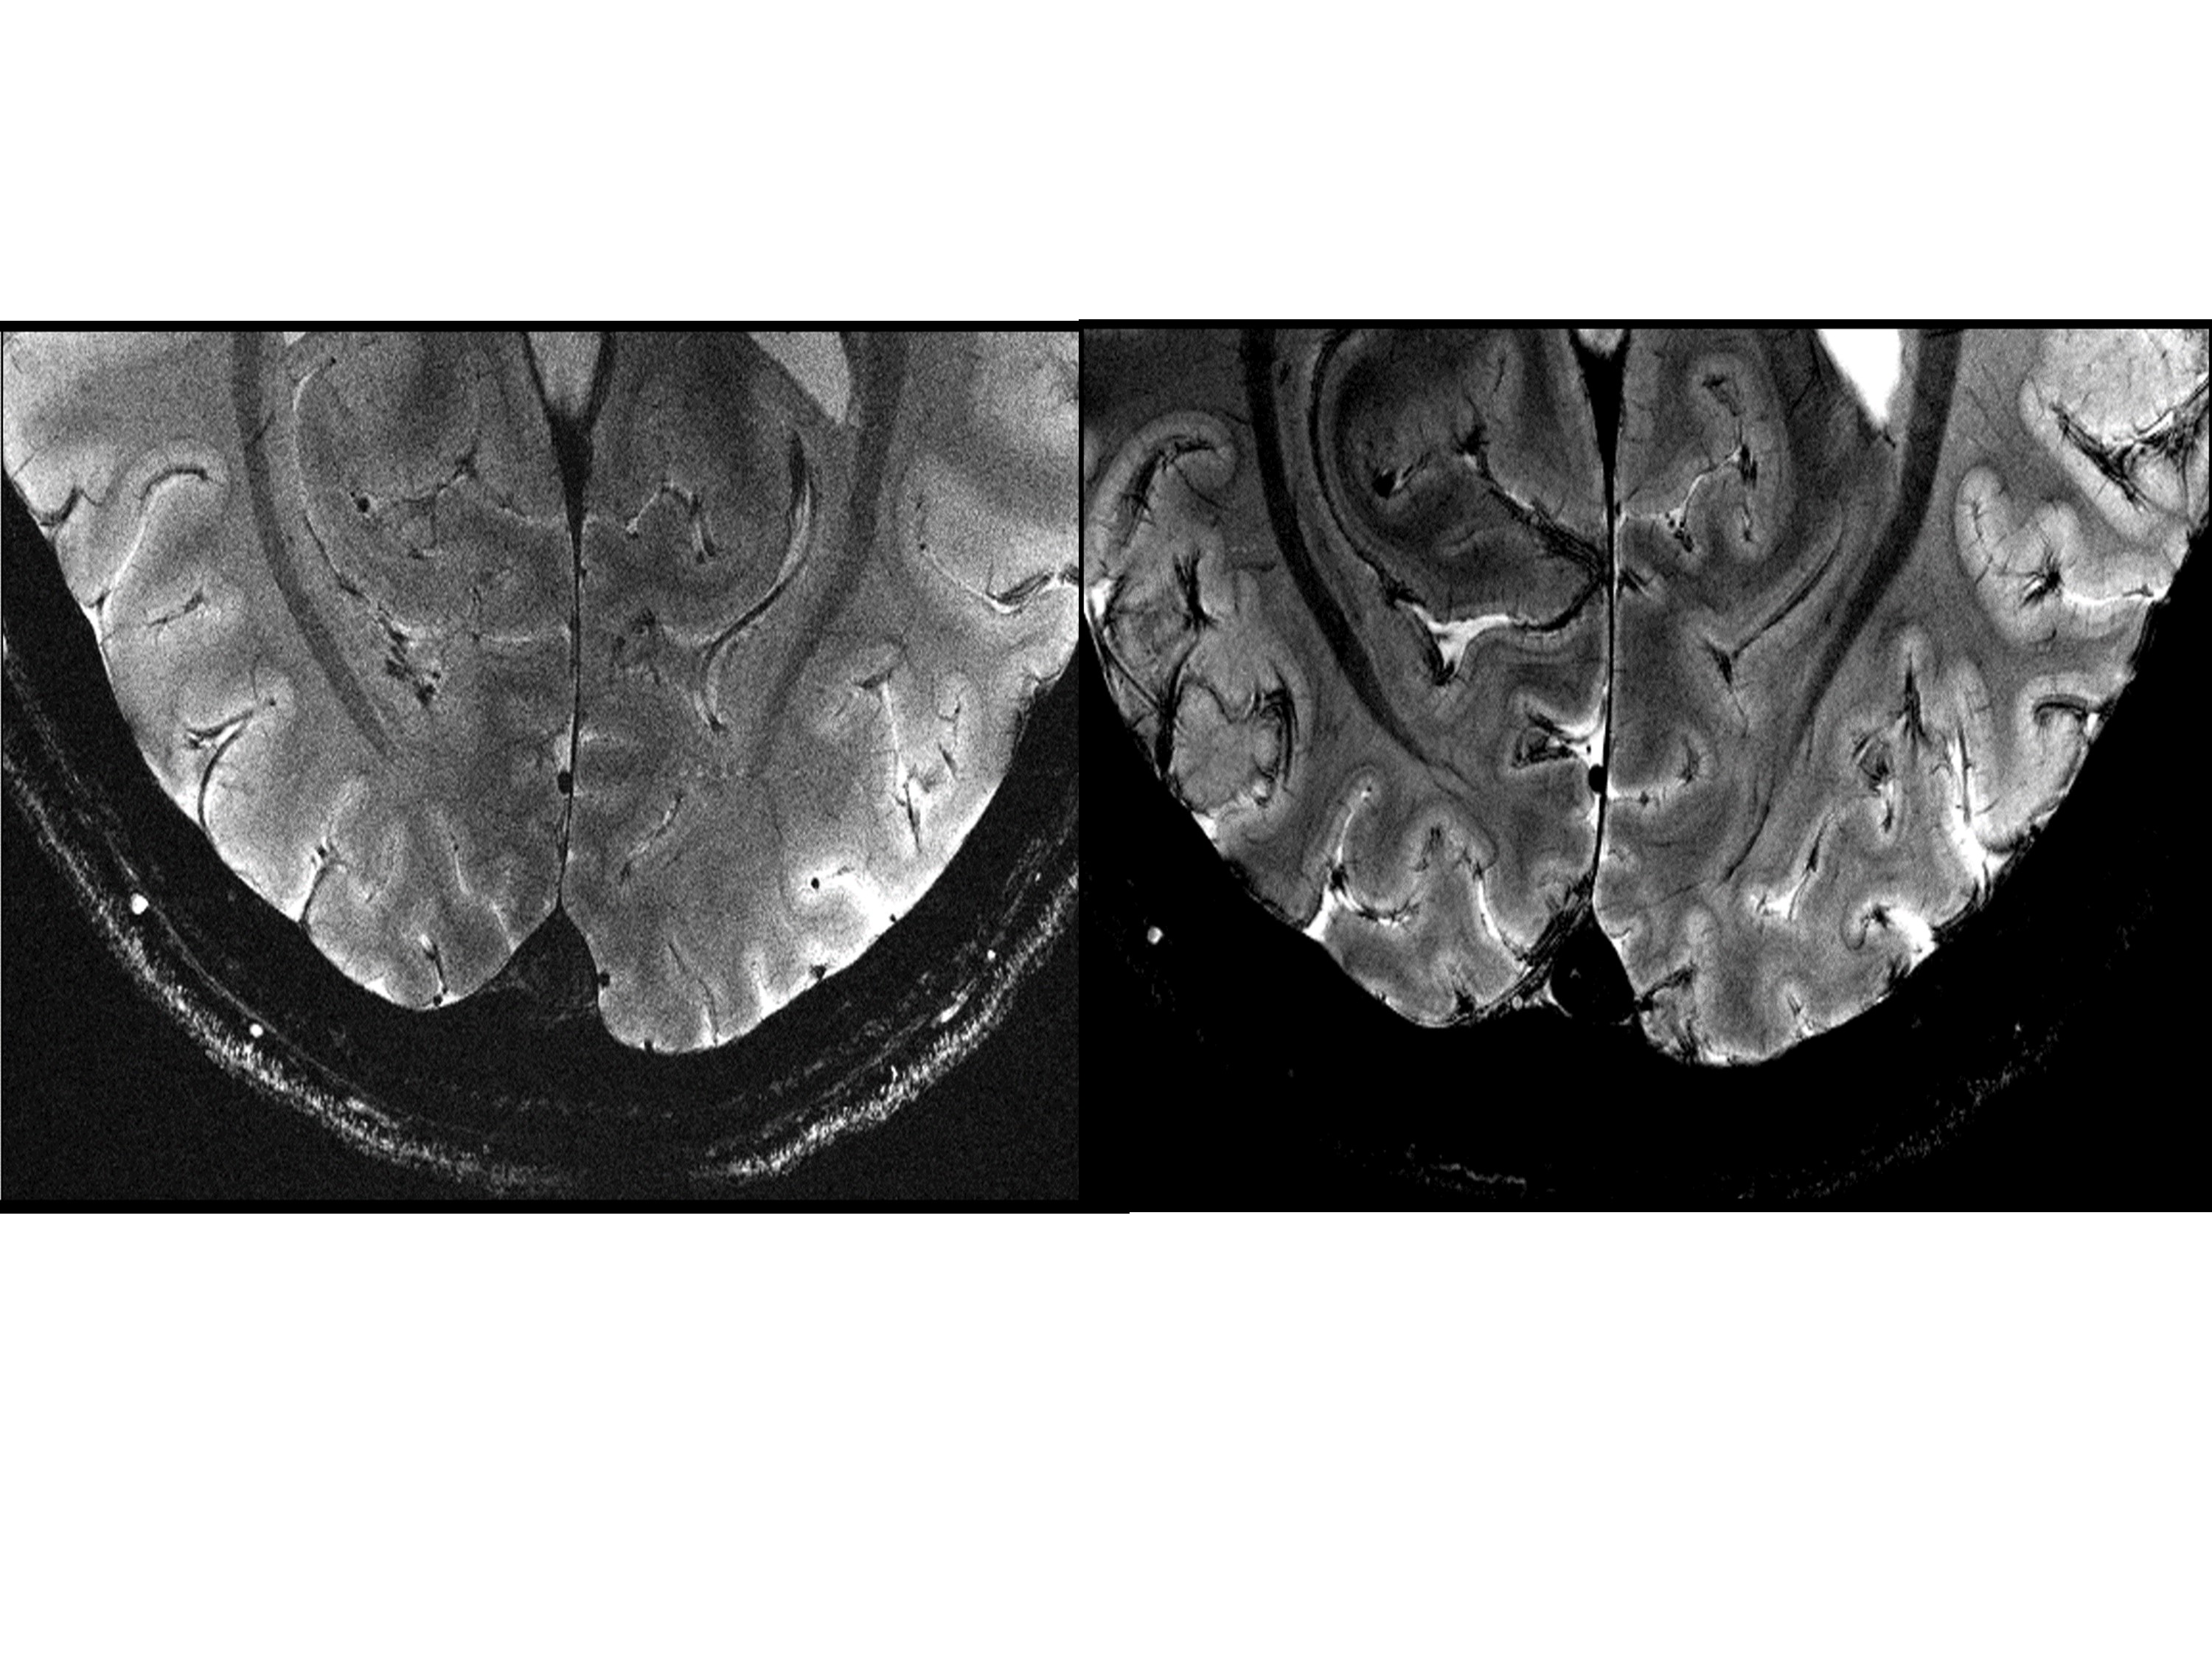

Figure.4: Comparison of 7T (left) versus 11.7T (right) images acquired in vivo, centered around the visual cortex.

Acquisitions were performed with resolution = 0.2 × 0.2 × 1 mm3, FA=27°, TE=20 ms, TR=0.6 s, bandwidth = 40 Hz/pixel, acquisition time = 4 min 20 s. Details within the cortical ribbon become clearly visible at 11.7T and not at 7T due to poorer signal and contrast to noise ratios.